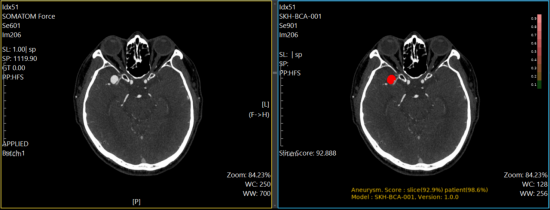

퍼플에이아이 박병준 대표는 "기존 뇌출혈 진단, 뇌경색 진단 AI에 이어 뇌동맥류 진단 AI 솔루션의 식약처 ... 조시영 기자2025.08.19 08:09E8, 이대서울병원과 AI 기반 뇌혈관 질환 진단 솔루션 개발